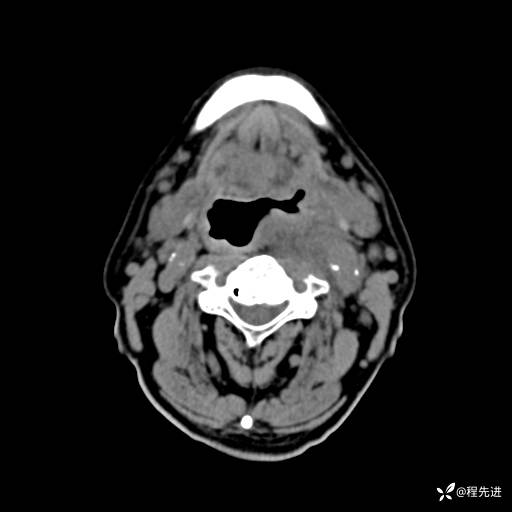

CT增强:

静脉期: